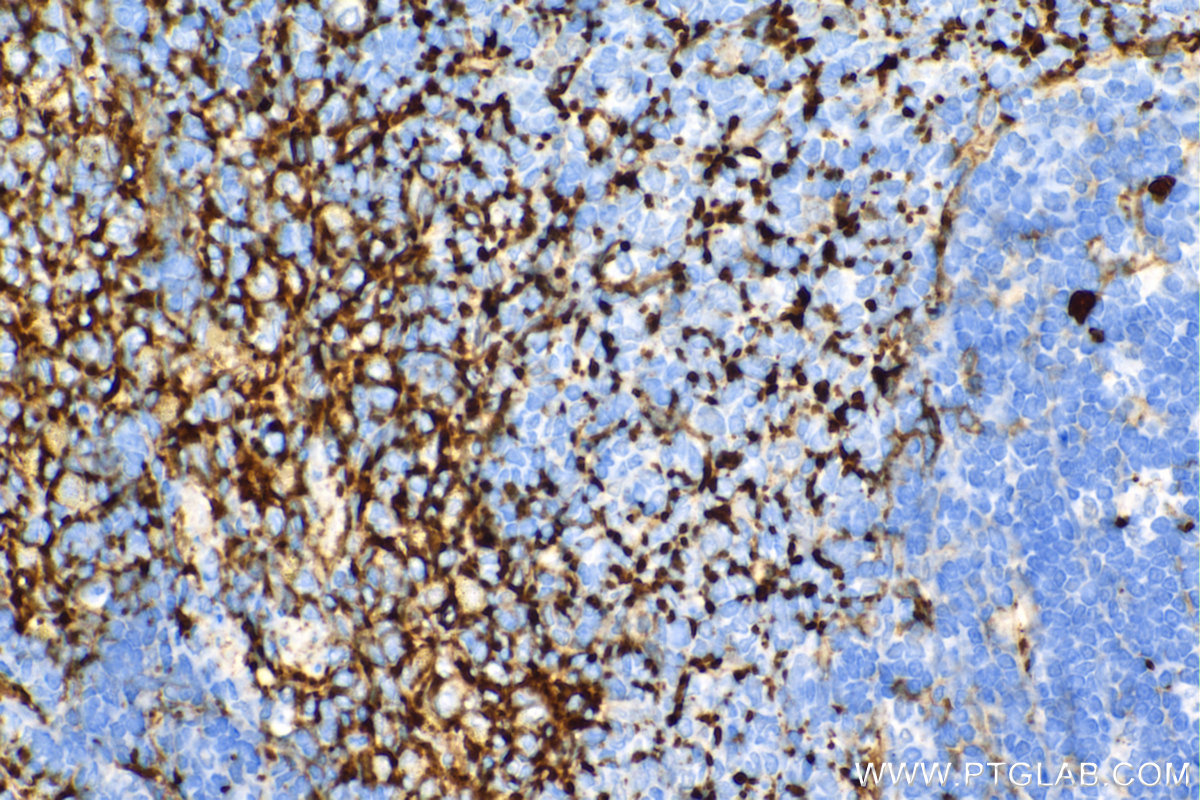

| Positive IHC detected in | mouse spleen tissue, human prostate cancer tissue, mouse kidney tissue, rat spleen tissue Note: suggested antigen retrieval with TE buffer pH 9.0; (*) Alternatively, antigen retrieval may be performed with citrate buffer pH 6.0 |

| Immunohistochemistry (IHC) | IHC : 1:1000-1:4000 |